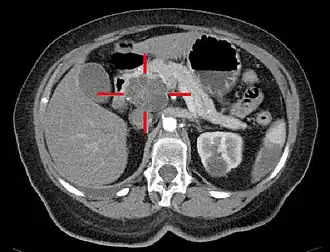

| TAC com coloração artificial e elevado nível de contraste. A cruz delimita um adenocarcinoma macrocístico na cabeça do pâncreas. | |